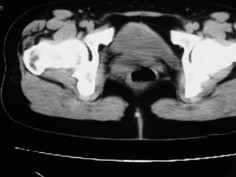

女42岁肛门下坠感4月余.

子宫轻度右倾,体后方见小似新月形低密度区,道格拉斯窝周围间隙欠清晰,有索条模糊影阴,多考虑:肛周脓肿可能性大。

子宫轻度右倾,体后方见小似新月形低密度区,道格拉斯窝周围间隙欠清晰,有索条模糊影阴,多考虑:肛周慢性感染可能。